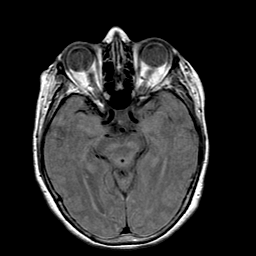

Stroke: proton density-weighted MR #1 -- Slice #10

[Home][Help][Clinical] Slice 10